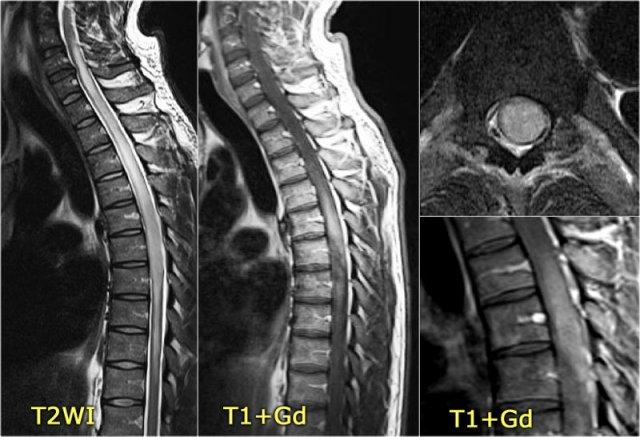

Đây là hình ảnh của một trường hợp điển hình.

Nhiều khi tiền sử lâm sàng rất hữu ích như trong trường hợp này.

Bệnh nhân nữ 24 tuổi có rối loạn thị giác một mắt, sau đó vài năm xuất hiện yếu và rối loạn cảm giác ở chi dưới và chi trên.

Hiện tại bệnh nhân đến khám vì rối loạn cảm giác ở cả hai chi dưới.

Vì vậy chúng ta đã nghĩ đến MS.

Trong tủy sống có một số tổn thương bờ rõ, nhưng cũng có một số tổn thương bờ không rõ, mờ nhạt.

Hình ảnh cắt ngang cho thấy vị trí ở phía lưng và hình dạng tam giác điển hình.

Tiếp tục xem các hình ảnh sau tiêm thuốc tương phản từ

Trên các hình ảnh sau tiêm thuốc tương phản từ, không thấy ngấm thuốc.

Các tổn thương MS hoạt động ở tủy sống có thể ngấm thuốc, nhưng không phổ biến như các tổn thương hoạt động ở não.